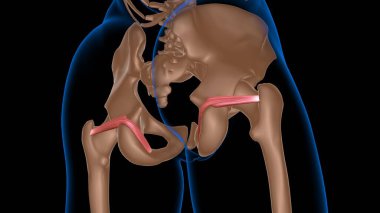

Tıbbi konsept 3 boyutlu illüstrasyon için insan kadın kas anatomisi

KasBileşenlerDorsalfleksörPalmarbrachiiBrevisLongusabdüktöradductorekstansiyonOrasına3d oluşturma3B illüstrasyonCarpiteresdeltoideusDigitorumbrachioradialiskomplikasyondigitiquintipollicisprofundusulnarispronatorPalmarisinterosseiopponenscoracobrachialisKas Anatomisilongus muscleinterossei musclebrevis musclelummbrical muscletricep mucslepollicis musclesuperficialis muscleBenzer İçerikler